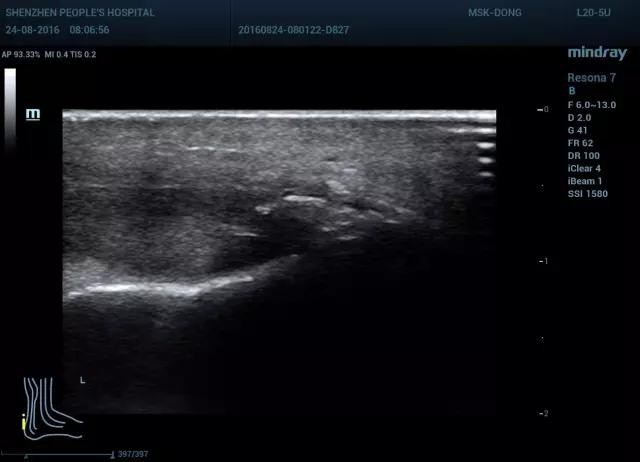

分腱周炎和跟腱炎,急性期跟腱肿胀,活动受限,慢性期疼痛减缓,有疼痛,运动后减缓。腱周炎超声表现为跟腱周围肿胀增厚,回声减低,可出现积液,但跟腱实质回声正常。而跟腱炎常表现为跟腱肿胀增厚,回声减低,实质不均匀,可累及部分或全部腱体,多继发跟骨后滑囊炎。

图9 腱周炎长轴双侧对比(图左 正常,图右 腱周增厚,回声减低,跟腱走行正常)

图10 腱周炎短轴双侧对比(图左 正常,图右 腱周增厚,回声减低,跟腱走行正常)